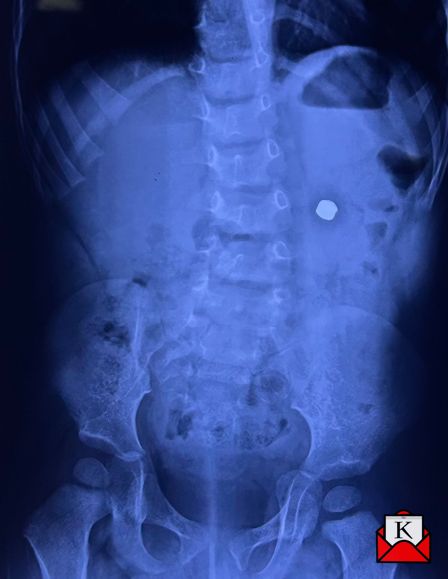

On May 2, 2025, baby Agastya was taken to the hospital due to stomach pain and green vomiting. A foreign object in the stomach was visible on an X-ray. The same evening, doctors attempted to remove it by endoscopy, but the battery was already deeply embedded in the stomach wall and could not be safely removed in that manner.